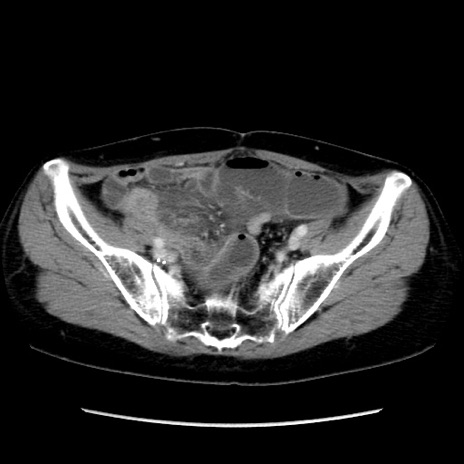

矢状断像

【症例】40歳代 女性

【主訴】上腹部痛、嘔気・嘔吐

【現病歴】約9時間前頃から急に上腹部痛、嘔気、嘔吐が出現。改善しないため救急要請。

【既往歴】子宮頚癌(広汎子宮全摘術、放射線療法)、腸閉塞

【身体所見】腹部:平坦、軟、腸雑音亢進、上腹部を中心に腹部全体に圧痛あり。

【データ】WBC 8400、CRP 0.03